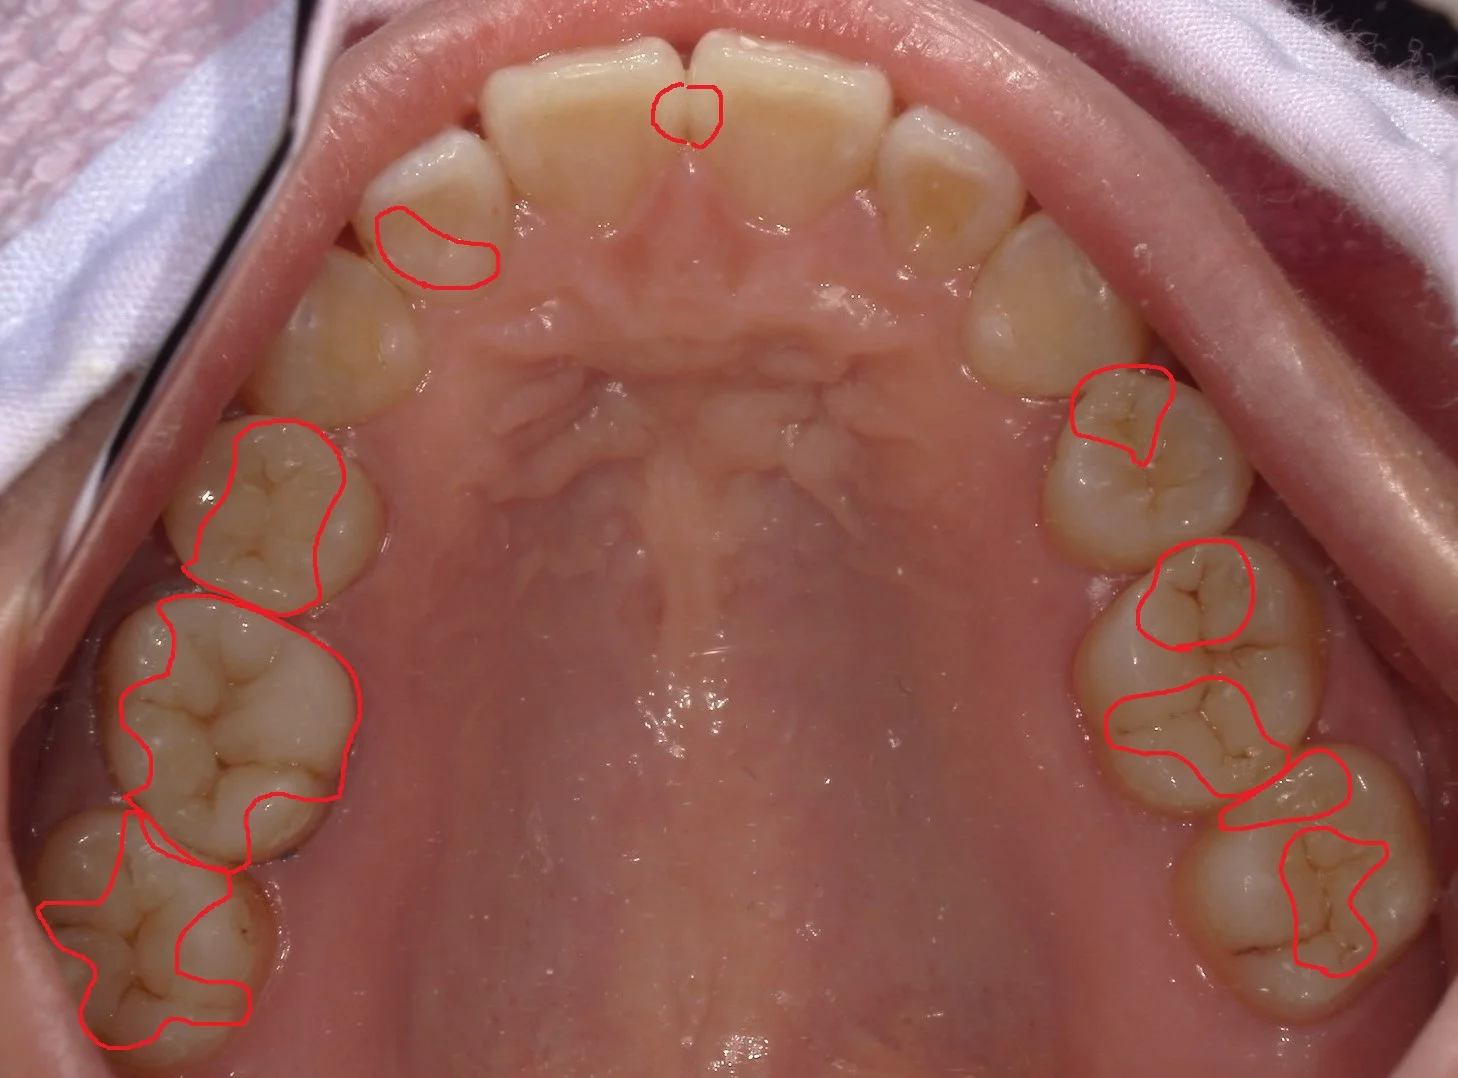

正解はこんな感じですヽ(゚∀゚)ノ パッ☆

計4回で治療終了まで行きました!